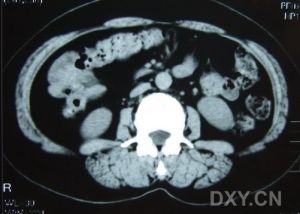

②逆行膽道造影、PTC、ERCP,可顯示狹窄部位、形態及範圍。膽管未顯影,不能除外膽管狹窄。有時靜脈膽道造影,也可顯示病變膽管。③B型超聲可示狹窄近端膽管擴張、或(和)結石的聲像圖。

4、“T”管逆行造影、靜脈膽道造影、PTC、ERCP等檢查,可顯示狹窄部位及形態。可行膽腸引流者,用對比造影法有助於診斷。